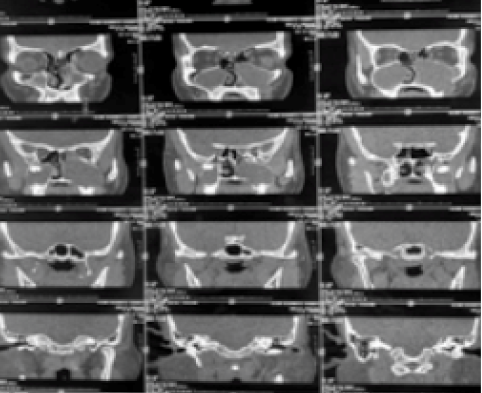

Patterns of Vascularization and Surgical Approach in Juvenile Naopharyngeal Angiofibroma

Rupanjita Sangma, Suhanee Goswami, Sharmistha Talukdar, Debojit Sarma